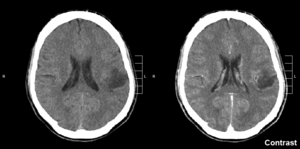

| Glioma in the left parietal lobe (brain CT scan), WHO grade 2. | |